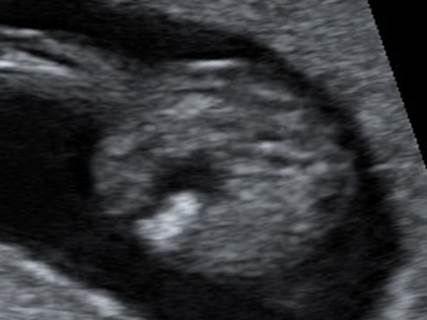

Вопрос 1

Это один случай в разные сроки в 12 и 21 неделю. Какой диагноз?

Ответ на вопрос 1

• Случай двойной атрезии — пищевода и 12-перстной кишки

• Признак «замкнутого» желудка, он смещен, перерастянут, симметричен (Travel подушка)